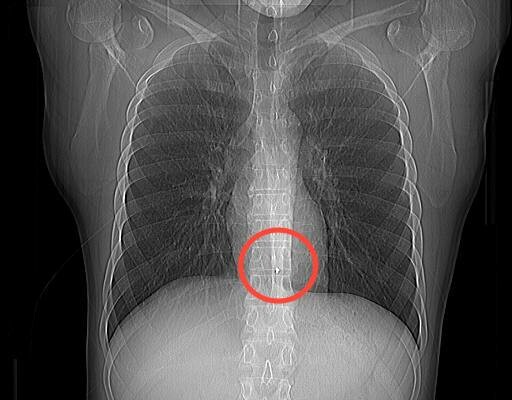

30-летний военнослужащий из Чувашии получил множественные ранения в зоне СВО в августе 2023 года. Произошло это при обстреле в одном из поселков Запорожской области. У бойца были задеты тонкий и толстый кишечник, желудок, сосуды и ткани брюшной области. Его прооперировали еще в Мариуполе, после чего он проходил реабилитацию в нескольких госпиталях. Но один осколок обнаружили чуть позже – он спрятался между аортой и пищеводом.

Сосудистые хирурги подготовили артерию на бедре, рентген-хирурги ввели специальный баллон, который при необходимости раздувается и перекрывает кровоток в аорте, на случай, если начнется кровотечение. Далее торакальные хирурги через минимальный разрез между ребрами зашли в грудную клетку и выделили участок аорты, где застрял осколок. Специалисты ввели назогастральный зонд в пищевод для того, чтобы локализовать и не повредить его. По данным КТ, торакальные хирурги определили примерное расположение осколка и пальцами осторожно нашли его.